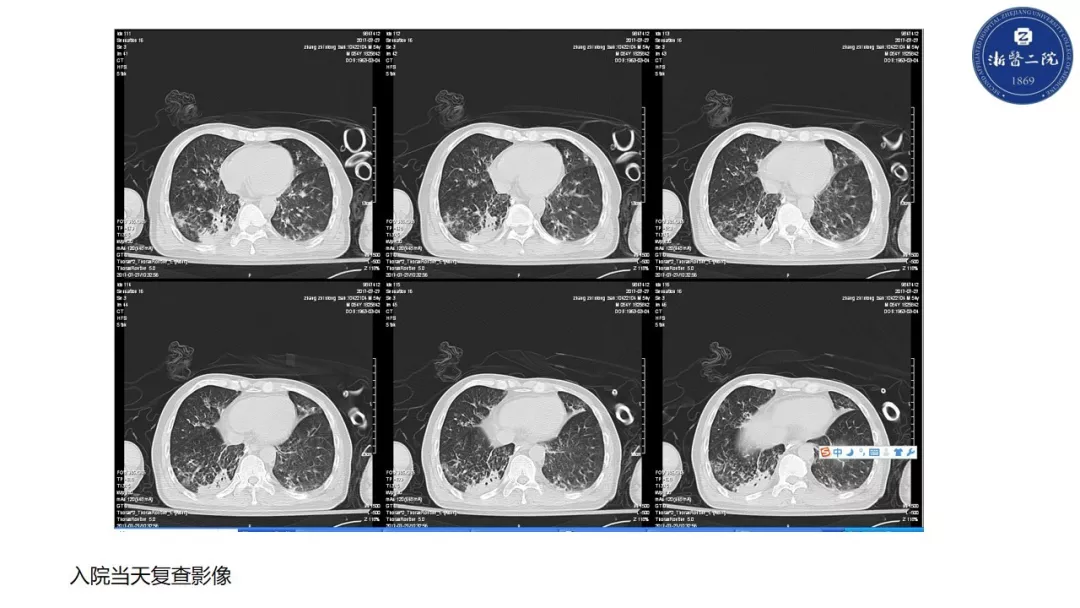

精彩点评 一、54岁男性,主要诊断:四脑室占位伴有幕上脑积水。术后病理诊断:颅内血管母细胞瘤。病人术后第四天,出现体温超过38.5度。 二、从诊断的思路上来讲,对于这种围手术期的病人。术后的体温升高,尤其是异常升高,首先,要考虑手术相关的颅内感染;其次,要考虑肺部感染的可能(因为病人术前就有右下肺的纹理增粗且有临床症状);再次考虑泌尿系感染的可能。下丘脑反应不应该考虑是此患者发热的原因之一。 三、可喜的是病人经过多学科协作积极治疗后,预后良好。尤其是在出现第6天出现意识变化后,经过气管插管及后期的气管切开等一系列积极的气道管理及重症管理,逆转了病情进展,而且术后脑脊液的循环通路完全通畅,没有梗阻性脑积水和炎症继发的交通性脑积水。第二,颅内感染经过后期的积极治疗,病人也达到临床治愈,但是,后期的脑脊液化验资料相对不全。 四、针对后颅窝操作围手术期感染的预防有如下建议: 1. 水密缝合硬膜以及手术后的伤口加压包扎是基本原则,此患者术前诊断为梗阻性脑积水。手术过程中如能提前放置脑室外引流,那么对手术以后的引流以及脑积液性状的观察均会有帮助,且防止术后出现颅内压增高; 2. 其次,病人有体温变化的时候,首先要查看伤口,并进行腰穿。化验脑脊液并送检细菌培养。这是一个基本的步骤,然后再进行经验性的用药,目前来讲脑脊液涂片的阳性率并不高,资料认为大概在5%-30%(北京协和医院资料大约为8%)。因此即使涂片阴性,也不能排除颅内感染的诊断。要综合考虑颅内感染的临床诊断; 3. 一旦诊断为是颅内革兰氏阳性菌感染,要进行经验性抗生素的调整,万古霉素、去甲万古霉素、利奈唑胺,均是有效药物,药物敏感性都非常好,要根据医院的流行病学情况、病人的个体差异,选择使用。 4. 要高度重视后颅窝手术后的气道管理,防止出现二氧化碳储留以及因吞咽障碍导致的误吸和肺炎。 魏俊吉 教授 北京协和医院神经外科副主任 北京协和医院神经急重症专业组组长 中国神经外科重症管理协作组副组长兼秘书长